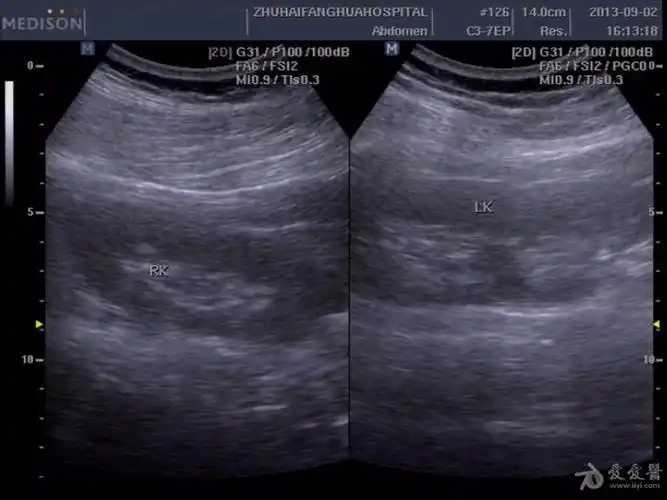

双肾盂

右侧双肾盂畸形!

胎儿双肾盂分离

左侧双肾盂